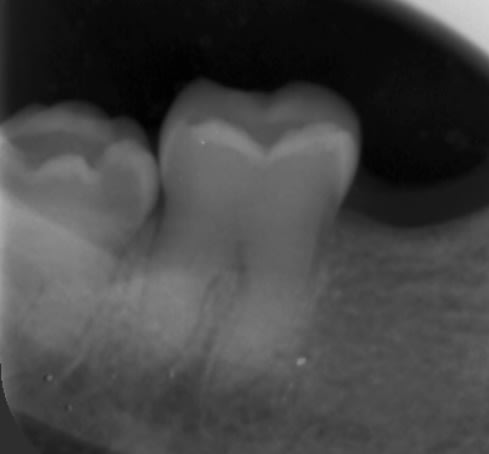

Radio 26

D9f30056 befd 4a58 a9d3 44fed132d3d4 zi8p3v - Eugenol

poignée de porte a diagnostiqué une maladie genetique, c'est un cas d'amélogenèse imparfaite avec racines courtes, obliteration des chambres pulpaires, émail fin et de mauvaise minéralité pour du collage... necrose en lien avec l'usure (les incisives inf)

il faudrait donc faire des élongations maousses , mais comme les racines sont courtes , ce sera des implants .